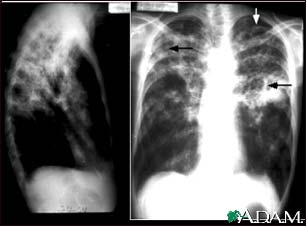

Tuberculosis, advanced - chest X-rays

Tuberculosis is an infectious disease that causes inflammation, the formation of tubercules and other growths within tissue, and can cause tissue death. These chest x-rays show advanced pulmonary tuberculosis. There are multiple light areas (opacities) of varying size that run together (coalesce). Arrows indicate the location of cavities within these light areas. The x-ray on the left clearly shows that the opacities are located in the upper area of the lungs toward the back. The appearance is typical for chronic pulmonary tuberculosis but may also occur with chronic pulmonary histiocytosis and chronic pulmonary coccidioidomycosis. Pulmonary tuberculosis is making a comeback with new resistant strains that are difficult to treat. Pulmonary tuberculosis is the most common form of the disease, but other organs can be infected.